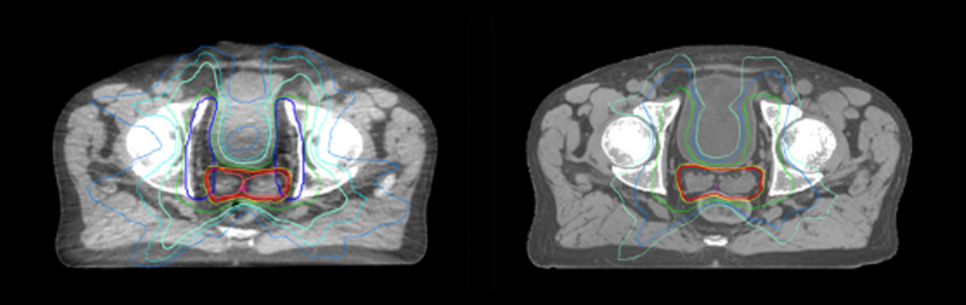

Dose plans overlaid on CBCT image dataset (left) and on MRCAT image dataset (right).

Evaluation of MRCAT dosimetric accuracy

Dosimetric equivalence validation was performed on 43 patient cases by comparing MRCAT-based dose plans overlaid on CBCT image dataset and on the corresponding MRCAT image dataset. Mr. Bolard and Dr. Champion found good agreement between MRCAT-based and CT-based dose calculations, with a mean dose ratio of 1.007 (0.991-1.014). The 3D gamma score was greater than 95% (95.2-99.0%) for all plans checked. A poster on this work was accepted for presentation at ESTRO 2020.

Mr. Bolard and Dr. Champion found good agreement between MRCAT-based and CT-based dose calculations, with a mean dose ratio of 1.007 (0.991-1.014).